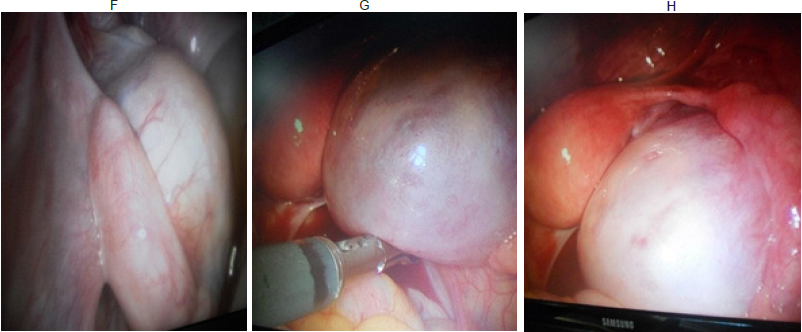

Basados en la clínica, los hallazgos a la ecografía abdomino- pélvica, TAC contrastada de abdomen y pelvis y resultados obtenidos en marcadores tumorales, se decide planificar abordaje laparoscópico de la tumoración descrita y biopsia intraoperatoria. Se realizó procedimiento quirúrgico con el hallazgo a la inspección de tumoración para uterina izquierda de aspecto quístico, útero central sin alteraciones y ovario derecho de aspecto y configuración externa normal con presencia de folículos en su superficie (Fig. 3 F, G, H) y presencia de líquido libre en cavidad abdominal y espacio retro uterino. La biopsia intraoperatoria por corte congelado revelo el diagnóstico presuntivo de posible “tumor de células de Sèrtoli-Leydig, histológicamente bien diferenciado”, albugínea y cápsula ovárica sin compromiso tumoral.